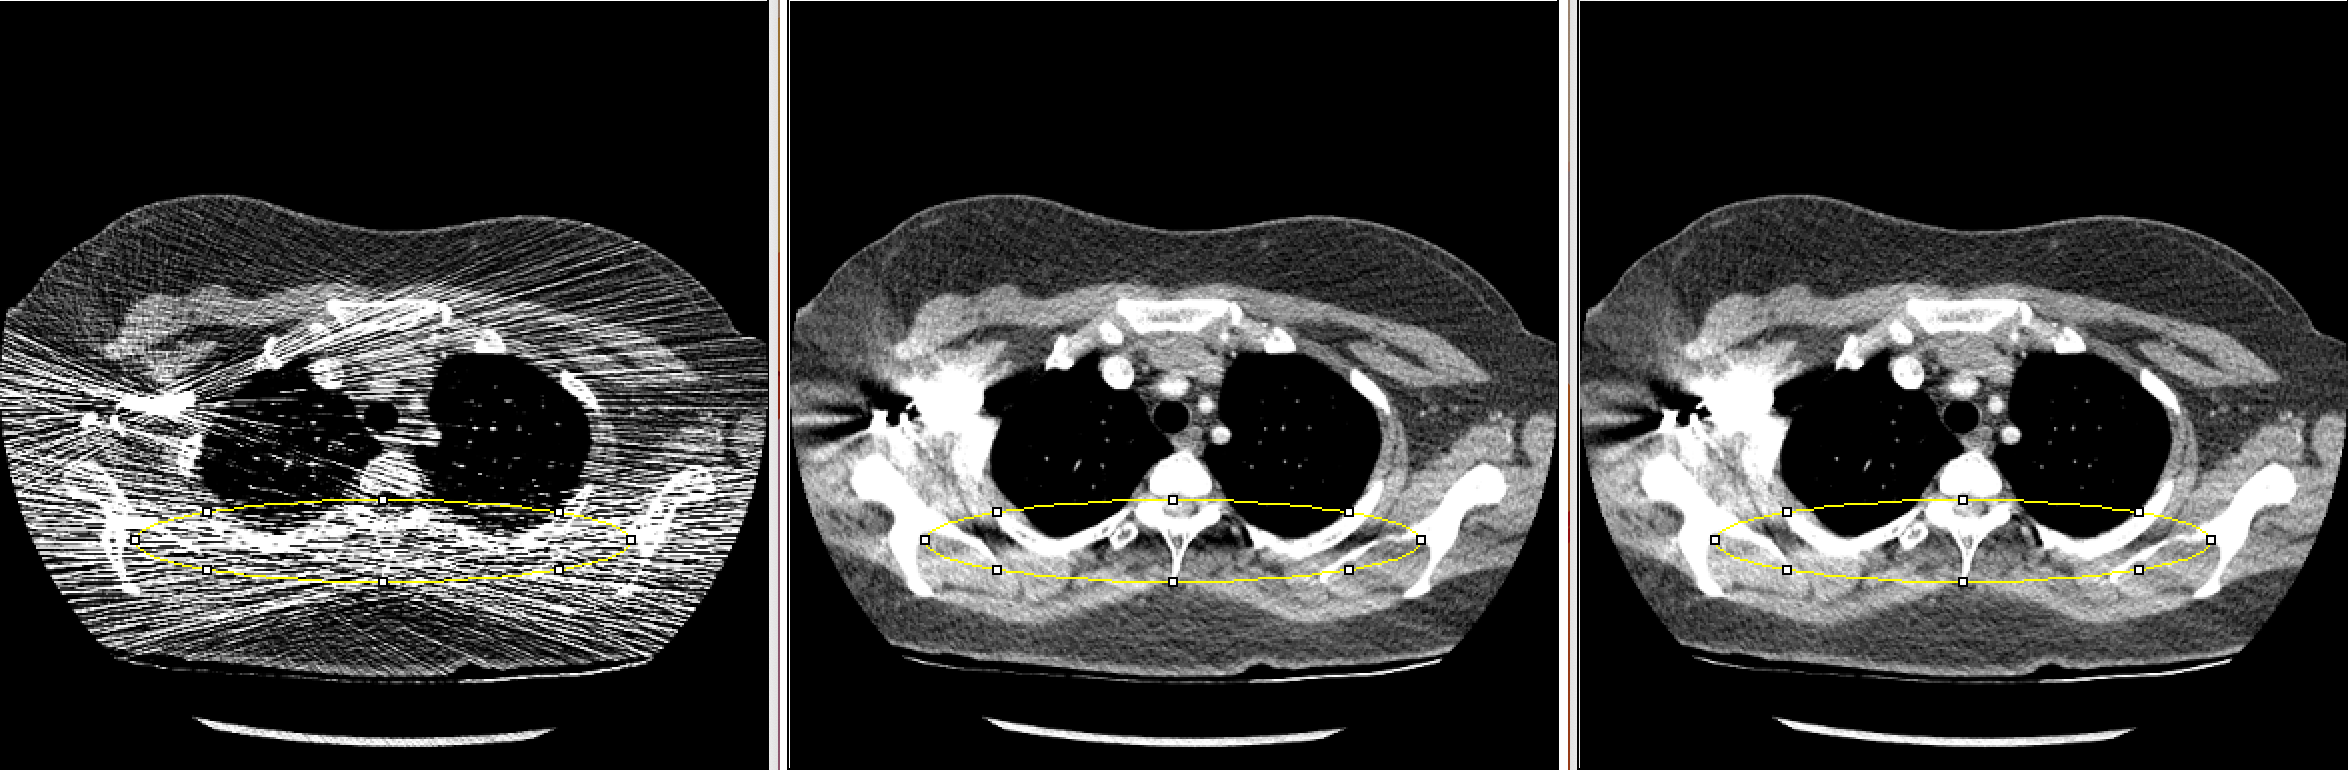

Figure 1: A slice of reconstructed image (left) Uncorrected, (center) FT LSC, (right) AF LSC LABEL:sub@fig:Exam1_70_imagej An axial slice of clinical image reconstruction in the liver region LABEL:sub@fig:Exam1_390_imagej An axial slice of clinical image reconstruction in the shoulder region containing contrast LABEL:sub@fig:Exam6_10 An axial slice of low signal phantom image reconstruction

It is clear that streaks are reduced in the FT LSC as well as AF LSC images. Compared with FT LSC, in AF LSC local averages in the reconstruction images were preserved, with slight reduction in local variance. In Fig. 1a, the liver region in AF LSC looks more uniform. In Fig. 1b, we see a reduction in low frequency bias around and below the spine.